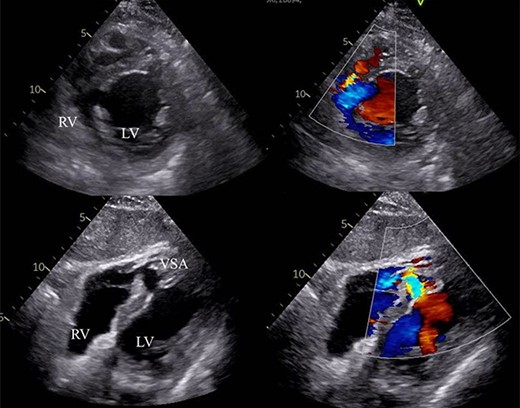

Laboratory data revealed hyperlipidemia and possible myocardial injury, as follows: creatinine kinase level of 202 IU/l, CK-MB level of 5.2 ng/ml, brain natriuretic peptide level of 412.6 pg/ml and Troponin T level of 1.58 ng/ml. Transthoracic echocardiogram (TTE) demonstrated mild pulmonary hypertension (PH), normal left ventricular ejection fraction (EF) of 67%, 15-mm VSA at the mid ventricular septum and ventricular septal rupture (VSR) of ~9 mm with estimated Qp/Qs of 2.56 (Fig. 2). Cardiac magnetic resonance imaging also recorded blood stream of shunt flow in VSA (Video 1). Moreover, coronary angiography revealed a 90% diameter stenosis of the right coronary artery and 75% lesion of the proximal left anterior descending coronary artery. Right catheterization revealed moderate PH and oxygen saturation increased due to LR shunt in the right ventricle (RV).

VSA with LR shunt flow. RV: right ventricle, LV: left ventricle, VSA: ventricular septal aneurysm.